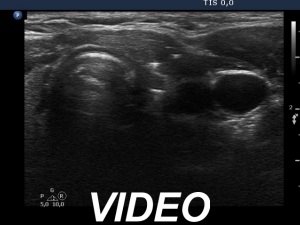

Ultrasonography revealed that the discrete hypoechoic lesion in the left lobe had increased in size, the dimensions were 4x4x5 mm, width, depth and length, respectively. There was a lymph node lateral to the left lobe. The node presented a heterogeneous pattern and lacked a regular hilum.Suggestion: repeat ultrasound in 3 to 6 months.

The small hypoechoic lesion within the left thyroid corresponds to a remnant. It seems to be realistic that this is thyroid tissue, but we have no particular reason to assume it would be a malignant lesion.

However, the lymph node is suspicious, especially due to its heterogeneity.